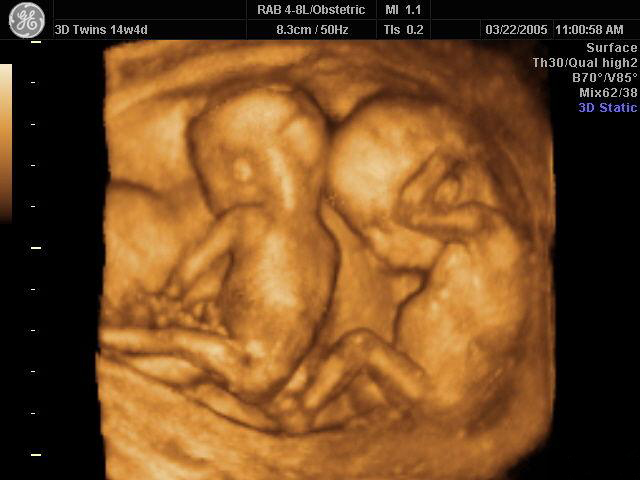

8.孕13-27周均属于中期妊娠。在此期间可以检测胎儿的生长发育情况,了解胎儿构造及羊水胎盘情况。

最后来个可爱的四维照!

有没有觉得宝宝可爱到爆!